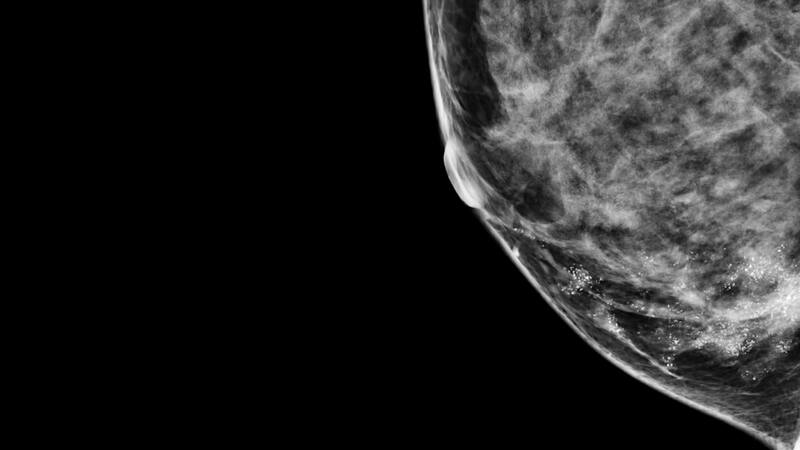

Una vacuna experimental contra el cáncer de mama ya podría estar salvando vidas

El 80 % de las mujeres vacunadas siguen vivas después de 10 años del inicio del tratamiento, obteniendo la remisión completa o conteniéndolo en gran medida.